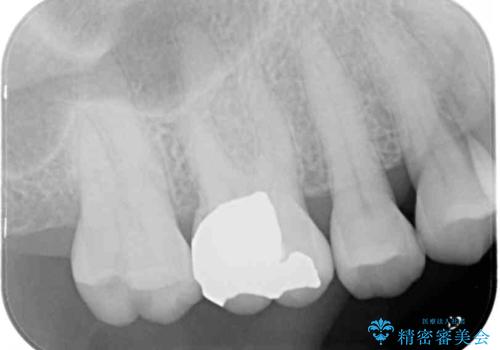

- 上の奥歯に装着されていた銀歯が外れてしまったとのことで来院された患者様です。

強い咬合力により銀歯と歯の間に隙間ができ、その隙間から虫歯となって外れてしまったと想像されました。

銀歯では歯と充填物の固さに違いがあり、再度外れてしまうリスクが高いため、固さが歯と近いゴールドインレー(PGAインレー)にて修復することとしました。

ゴールドインレーは銀歯のインレーやセラミックインレーと比べ、「技工操作の精度が高く、適合が著しく良い」というメリットがあります。特に上の奥歯は歯科医師の操作が行いにくいため、「適合の良さ」は再治療のリスクを防ぐ上でとても重要な要素となります。